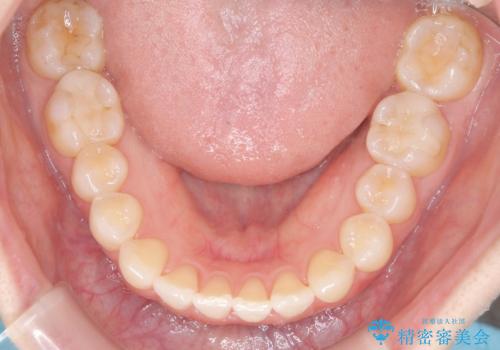

前歯と奥歯のガタガタを矯正で改善

- 患者様は、前歯と奥歯のガタガタ(叢生)を改善し、正面から見た時の歯並びを美しく整えたいとのご要望で来院されました。診断の結果、非抜歯での矯正が可能と判断し、インビザラインを使用する治療計画を立案しました。透明な矯正装置で目立ちにくい治療を行いながら、前歯と奥歯の両方を整列させることを目標にしました。

インビザラインを用いて、前歯の見た目を重視しつつ、奥歯のガタガタも改善しました。特に正面から見た際の美しい歯列を意識し、段階的に歯を移動させることで、全体の調和を図りました。治療中は、適切な装着時間を守ることや、装置の清潔を保つことが重要でした。また、歯肉や歯列全体に無理な負担がかからないように移動を管理しながら治療を進めました。結果として、前歯と奥歯がきれいに並び、見た目にも機能的にも満足いただける仕上がりとなりました。